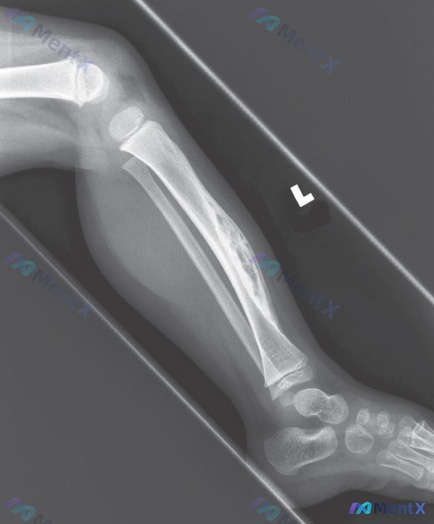

整理了一个很有警示意义的病例,感觉很容易被带偏,分享一下思路: 病例核心信息 - 患者:8岁男孩 - 主诉:跛行 - 关键影像: 1. 左小腿正位X光:胫骨骨干中下段内侧见一局灶性、边界清晰的类圆形透亮区,周边可见硬化缘;骨皮质连续,无骨折,关节关系正常,软组织无肿胀 2. 腕部MRI:T1加权桡骨...

看到一个很有警示意义的病例,整理一下临床思路: 病例核心信息 - 患者:15岁男性 - 主诉:腿部疼痛 - 关键病史:阿司匹林或布洛芬治疗无改善 - 影像检查:小腿X光侧位片 影像报告客观所见(按提供的分析) - 骨皮质连续,未见明确骨折线、移位 - 未见明显的溶骨性/成骨性骨质破坏,未见明确占位...